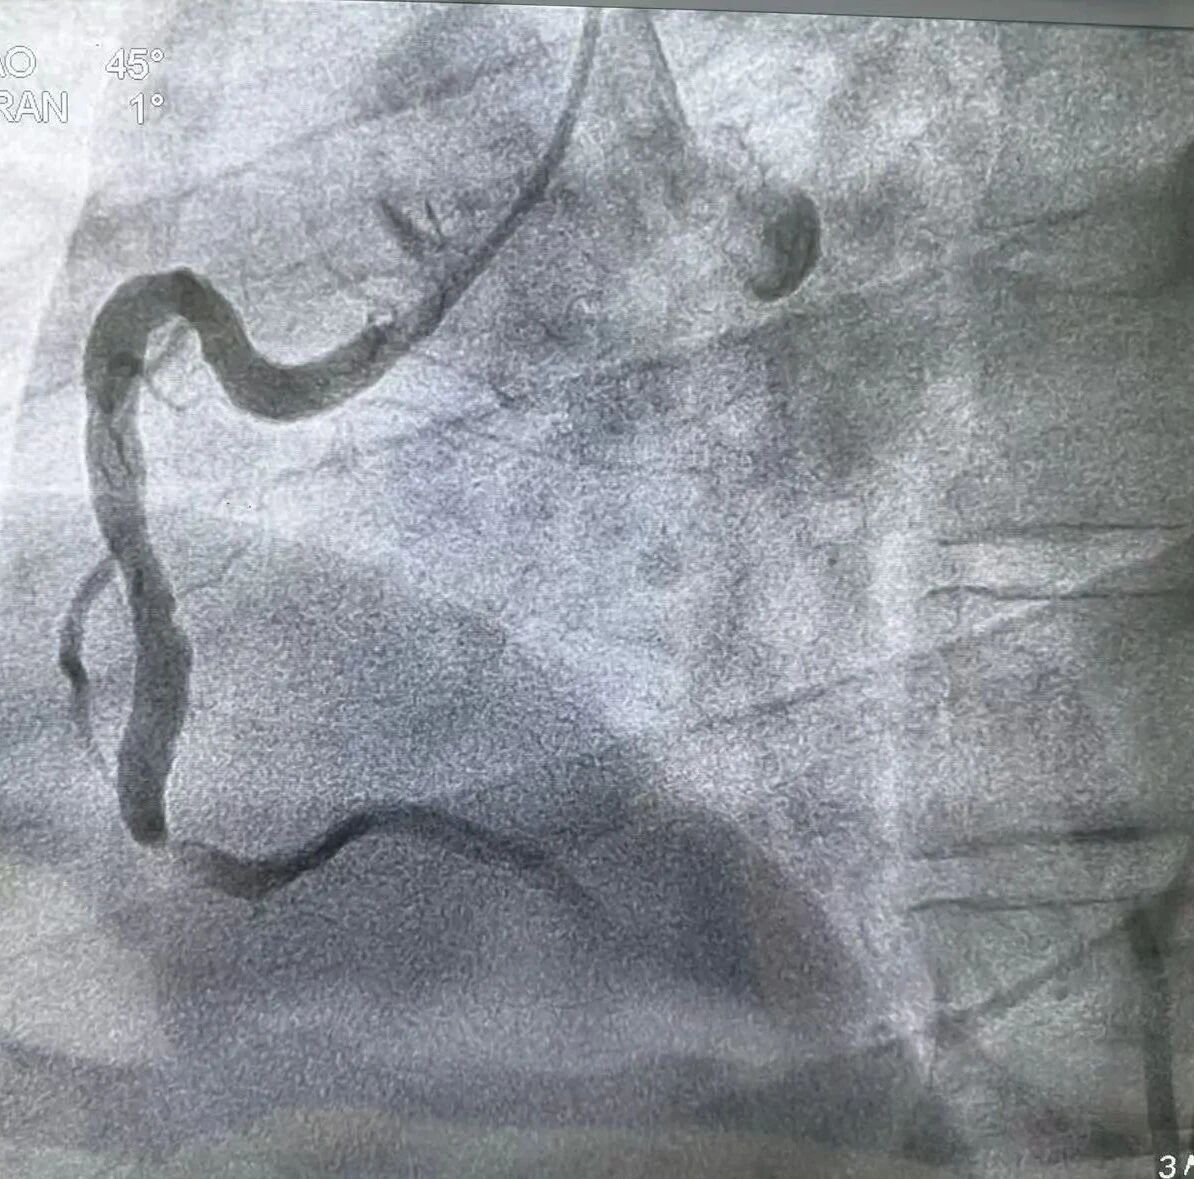

近日,一名34岁男性李某因突发胸痛1.5小时,被紧急送至周口人合医院急诊科。心电图提示“急性下壁心肌梗死”,情况危急!医院胸痛中心绿色通道立即激活,急诊冠脉造影显示右冠中段次全闭塞。医护团队迅速行动,快速开通闭塞血管并实施药物球囊扩张成形术,D2W(入门至导丝通过)时间仅31分钟,远低于国际标准90分钟!术后患者恢复良好,现已转危为安。

快速开通闭塞血管并实施药物球囊扩张成形术

术前